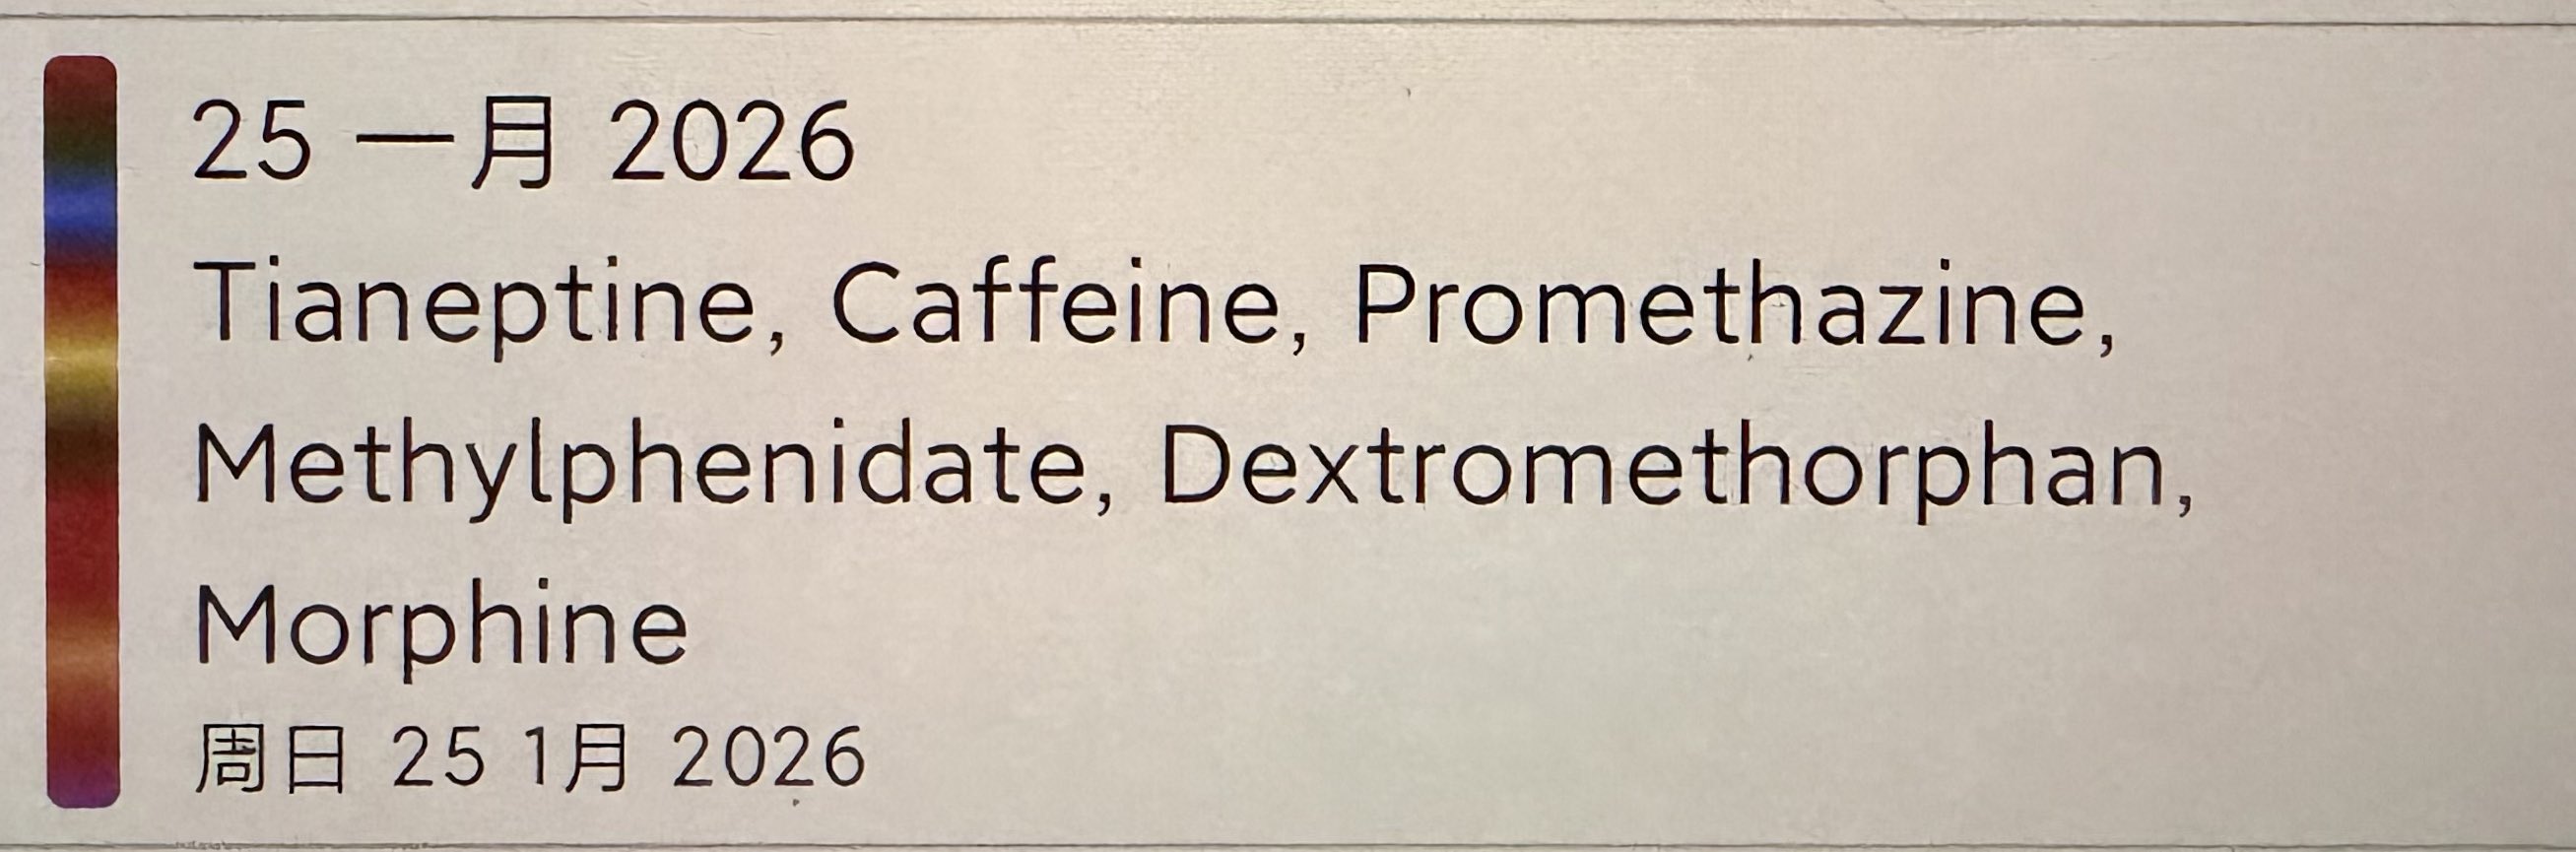

炽烈已极 @AnIncandescence日历里都是机的问候…幸福 https://t.co/GRT8h2mo2l